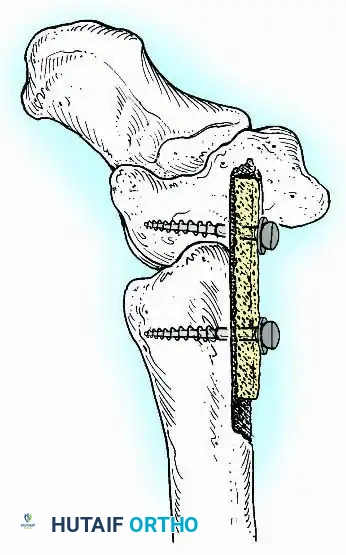

For complex hindfoot reconstructions, specialized plating systems, including anterior or lateral locking plates, can be utilized to supplement screw fixation, particularly when structural allografts are required to restore limb length.

Knee Arthrodesis

While total knee arthroplasty (TKA) is the definitive treatment for knee osteoarthritis, knee arthrodesis remains a critical salvage procedure. The primary indications are a chronically infected TKA that has failed two-stage revision, massive extensor mechanism disruption, severe neuropathic arthropathy, and tumor resection.

Positioning and Technique

The optimal position for knee arthrodesis is 10 to 15 degrees of flexion and 5 to 7 degrees of valgus. This slight flexion assists in foot clearance during the swing phase of gait and makes sitting in confined spaces more manageable. A perfectly straight (0 degrees) knee is cosmetically awkward and functionally detrimental, causing a vaulting gait pattern.